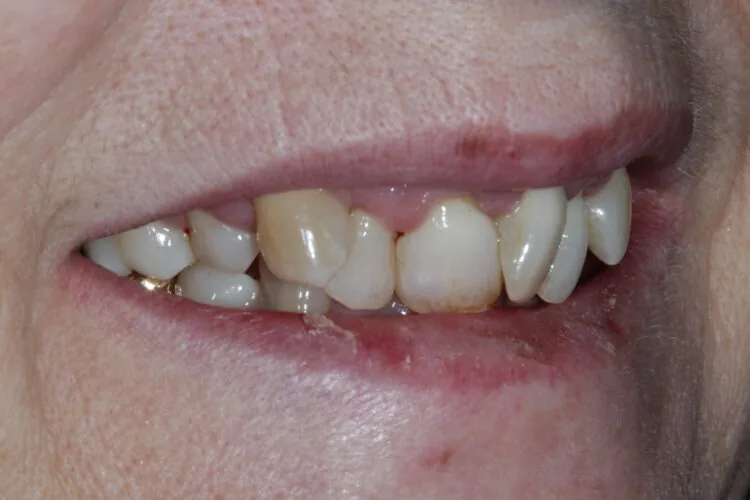

A woman in her mid-50s presented with the desire to improve her smile. She had not attended dental appointments for several years and felt ashamed of her teeth due to longstanding neglect. At the time of presentation, she had significant periodontal deterioration, particularly involving the upper four anterior teeth, which exhibited bone loss and mobility. Although she initially requested orthodontic treatment, this was not viable due to the advanced periodontal condition

Presenting condition

A comprehensive periodontal examination revealed widespread pocketing and clinical signs of mobility in the anterior region. The upper central and lateral incisors were the most severely affected, and they showed persistent instability despite improvements elsewhere. Generalised recession and attachment loss were confirmed, with periodontal charting from September 2023 and follow-up data in November 2023 demonstrating the extent of disease and its subsequent management.

Pre-treatment images